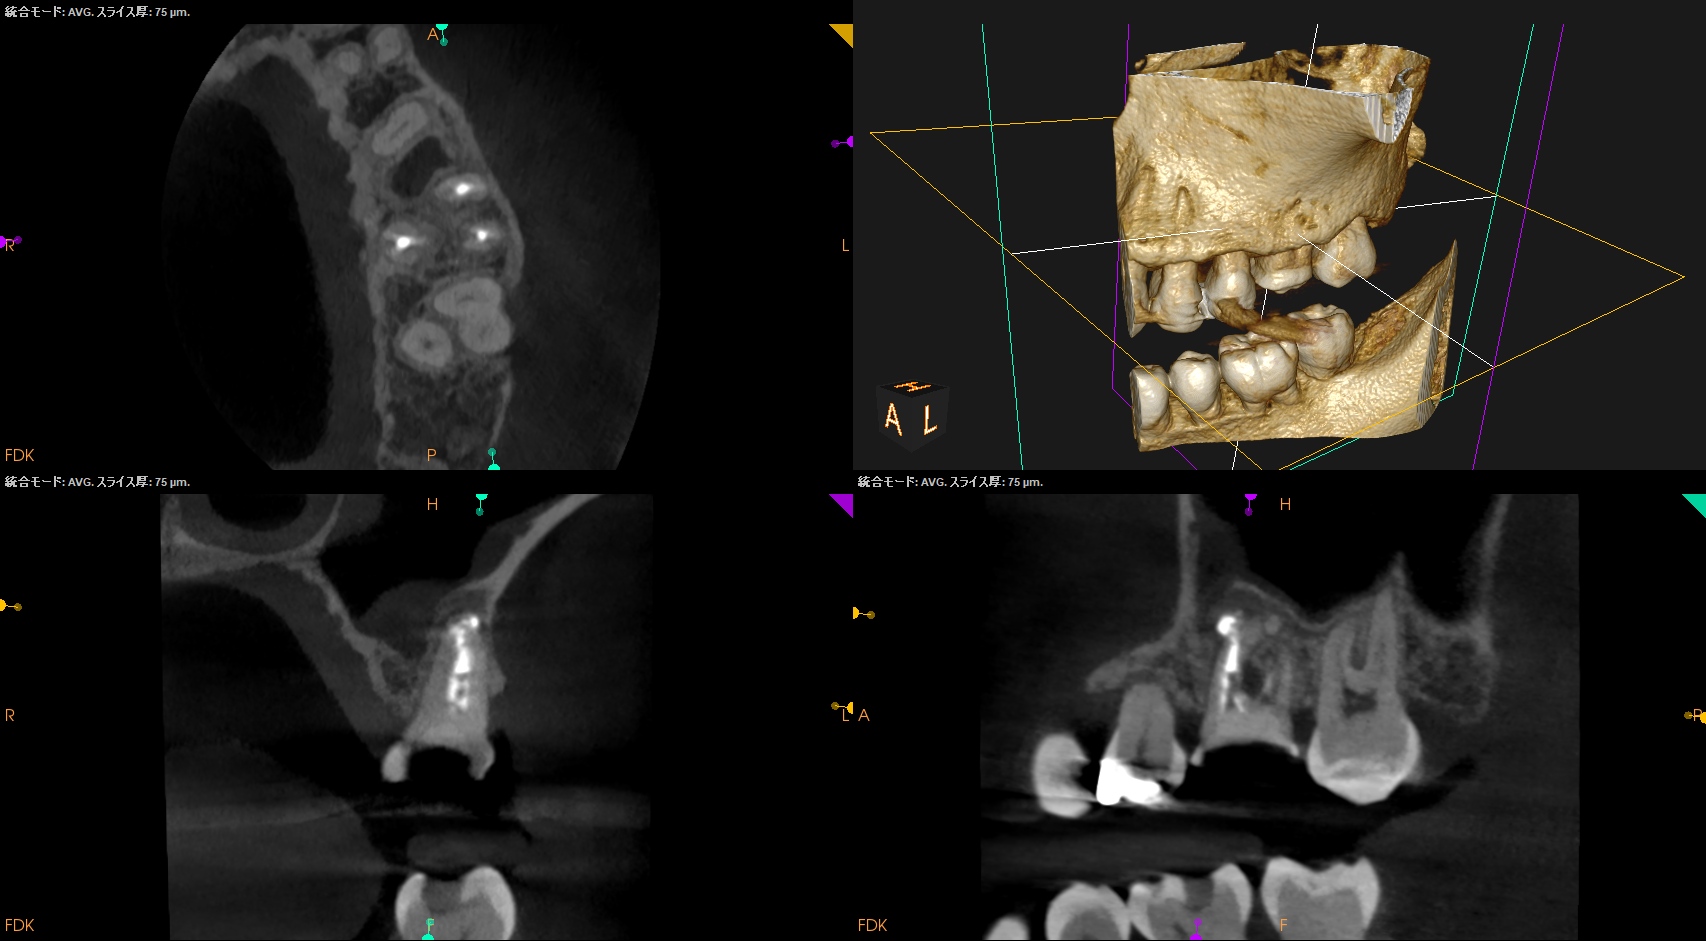

術後にPA, CBCTを撮影した。

問題はないだろう。

#14 Core build up, Perforation Repair(2025.4.15)

MBは穿孔部ごとBC sealer, BC Puttyで充填した。

この後Apicoectomyになるから問題はない。

同日、MBのApicoectomyを行った。

MBのApexを見つけることなく、CEJから5.5mmの位置で頬舌的幅径5mmの長さで切断し、Apex周囲の骨を削除しApexを取り除いた。

その後、メチレンブルーで染色し逆根管形成に移行する。

その際はBC sealerのみであるのでGutta Percha Pointの残渣に悩まされることがない。かなり時短できるだろう。非常にEasyなApicoectomyだ。

これが私が穿孔封鎖とApicoectomyを同日に行なった理由である。